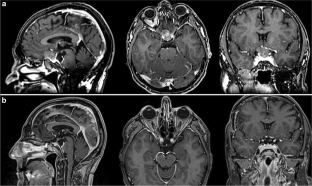

Fig. 1

Fig. 2